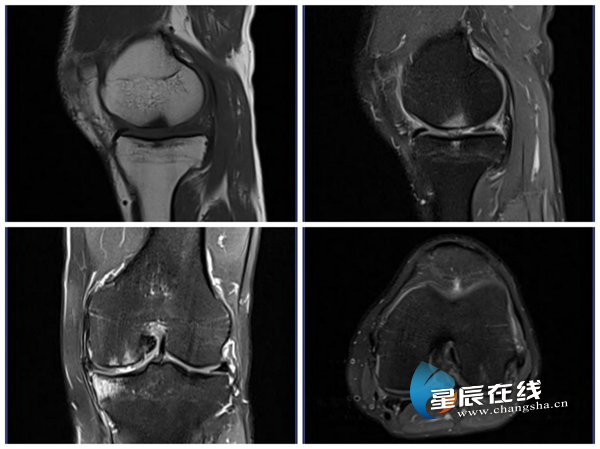

核磁共振(MRI)没有辐射,利用磁场和无线电波让人体内的氢原子振动,接收信号后成像。它对肌肉、韧带、大脑、脊髓等软组织显示特别清晰,常用来诊断关节损伤、脑肿瘤、椎间盘突出等。

(膝关节核磁共振影像示例,清晰显示半月板与韧带。图片均由 通讯员 提供)